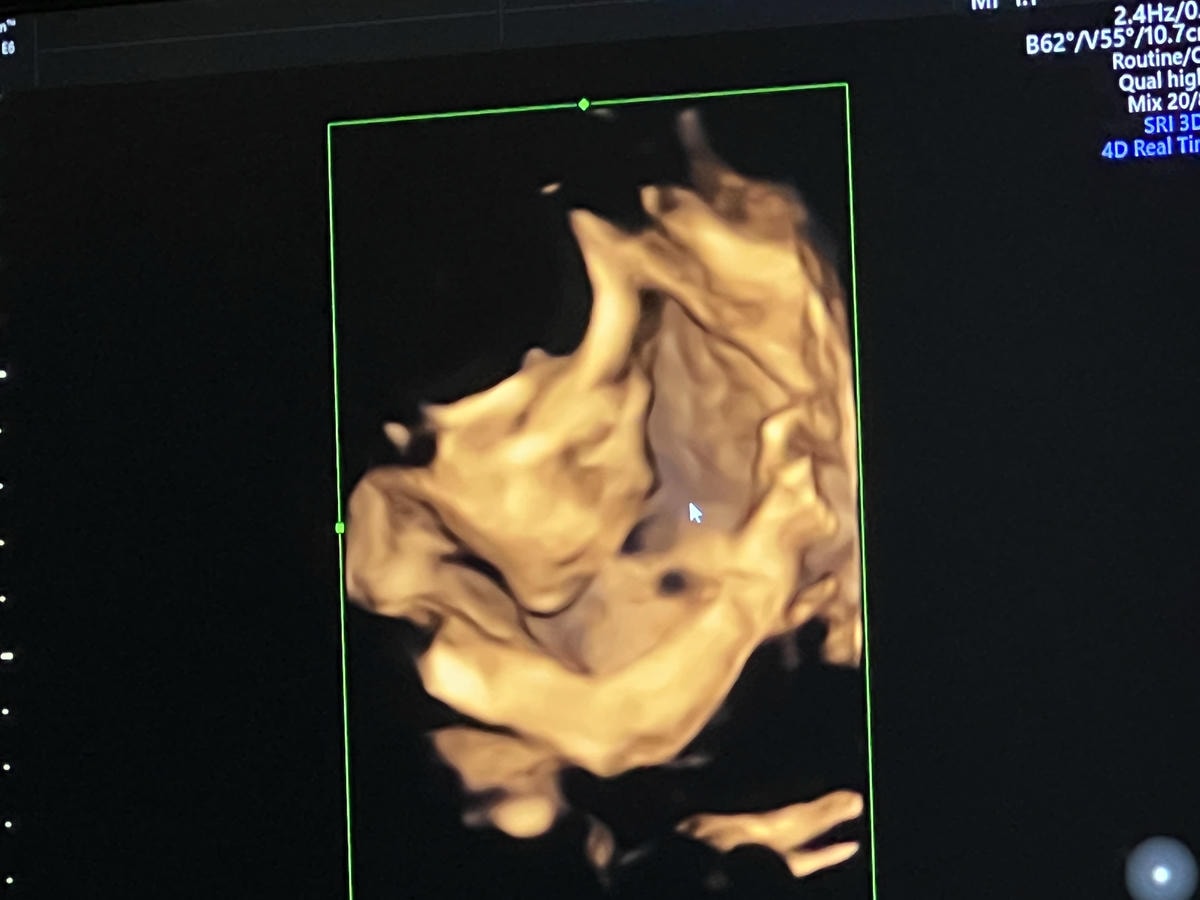

看完寶寶的發展大小就要進入我最最最期待的部分,蕙生醫院最新引進 3D/4D超音波

不用在看黑黑的超音波螢幕,來到這邊寶寶的一舉一動看的超!清!楚!

寶寶今天算給我一點點面子能看見側面的部份,因為寶寶的臉卡在我的胎盤下面,

所以要完完全全看見整張臉有點困難,院長人也超好一直努力幫我盡可能看見寶寶的樣子

這次來到蕙生醫院產檢,醫院在九月份引進了新儀器,可以讓孕媽媽們看到超清楚的寶寶

院長說3D/4D超音波的範圍只有在下面框框裡,如果寶寶貼著胎盤角度也就會不好看見

也有拿到寶寶的超音波照片,照的好清楚喔 比我自己看的婦產科還清楚超多

最近產檢完全不知道照片在拍什麼… 謝謝蕙生醫院讓我看到超清楚的寶寶照可以留念